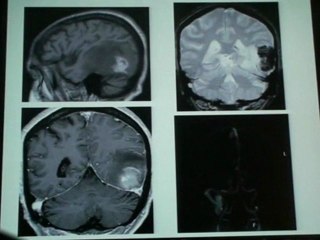

Doctor Sounds Alarm About Certain Type of Sudden, Severe Headache